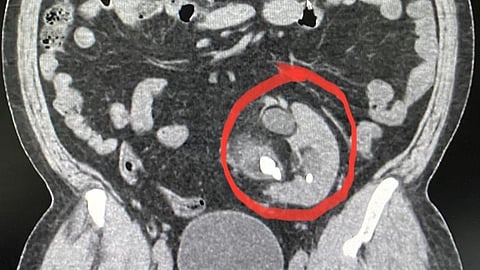

وكان المريض قد حضر إلى العيادة وهو يعاني آلامًا مزمنة في البطن، وبعد إجراء الفحوصات المخبرية والأشعة اللازمة؛ تبين وجود كلية في غير مكانها الطبيعي في الحوض أسفل البطن، مع وجود حصوات متعددة، وانسداد في مخرج حوض الكلية، إضافة إلى تأخر في وظيفة الكلية.

وبيّن التقرير أنه بعد تحضير المريض لغرفة العمليات لإجراء عملية جراحية لإعادة مخرج الكلية واستخراج الحصوات مع تصحيح للانسداد؛ تكللت العملية بالنجاح، وتحسنت حالة المريض حتى غادر المستشفى بصحة جيدة.